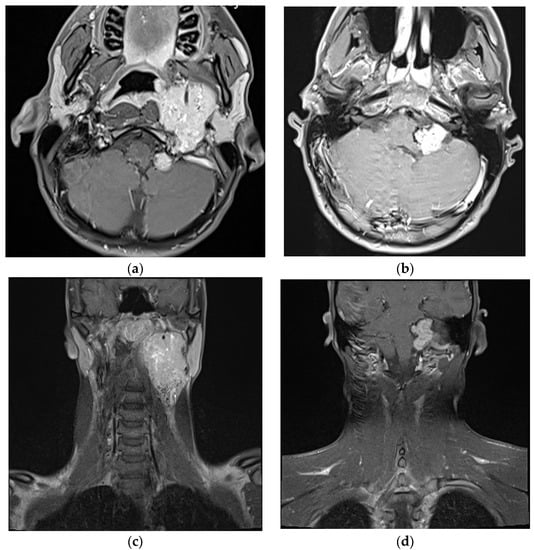

3.3.1. Case 1

3.3.2. Case 2